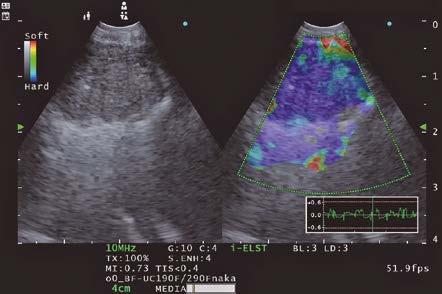

ELST Mode (i-ELST)

The selection of the puncture site was determined by using the ELST mode. The EU-ME3 with its newly equipped “i-ELST function”, enables to display stable ELST images even with minute vibrations. The ELST images were green at the center of the lymph node and predominantly blue at the margins of the lymph node.

It has been reported that a combination of ELST and B-mode images is useful for identifying the most suspected site of the lymph node when performing EBUS-TBNA.*

As described above, we were able to collect viable tumor cells and the core by adjusting the puncture site and puncturing the node referring to the ELST mode images.